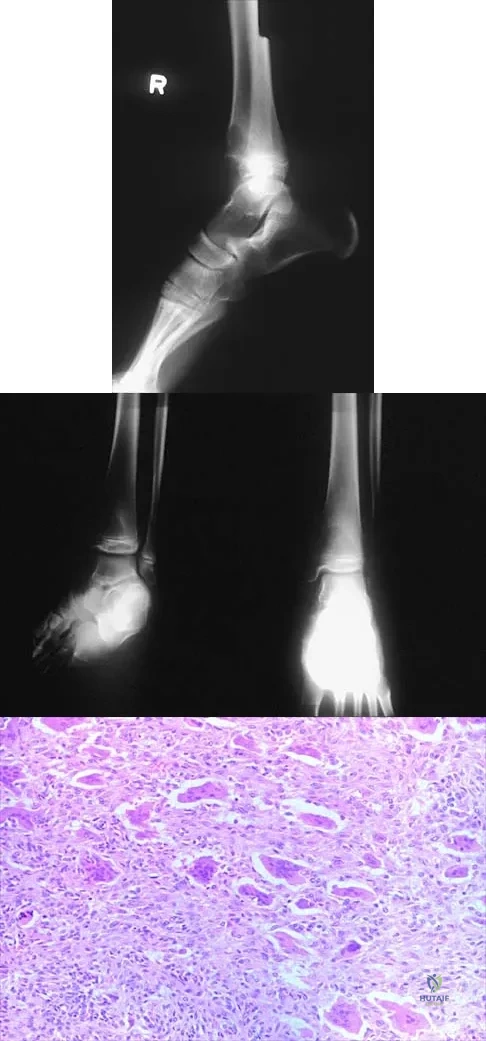

Figures 52a and 52b show the plain radiographs of a 12-year-old girl who has right distal leg pain. She reports that symptoms are present with weight-bearing activities and improve with rest. Examination reveals diffuse tenderness over the distal tibial metaphysis and mild swelling. A photomicrograph of the biopsy specimen is shown in Figure 52c. What is the most likely diagnosis?

Explanation

A 19-year-old girl has had pain and swelling in the right ankle for the past 4 months. She denies any history of trauma. Examination reveals a small soft-tissue mass over the anterior aspect of the ankle and slight pain with range of motion of the ankle joint. The examination is otherwise unremarkable. A radiograph and MRI scan are shown in Figures 45a and 45b, and biopsy specimens are shown in Figures 45c and 45d. What is the most likely diagnosis?

Explanation